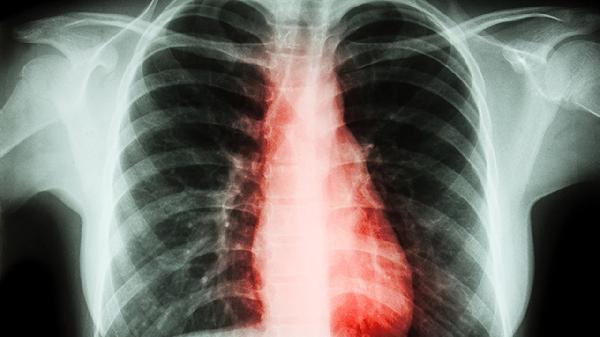

胸椎痛可能由肌肉劳损、骨质疏松、胸椎间盘突出、胸椎关节紊乱、强直性脊柱炎等原因引起。胸椎痛通常表现为局部疼痛、活动受限、放射痛等症状,可通过物理治疗、药物治疗、手术治疗等方式缓解。